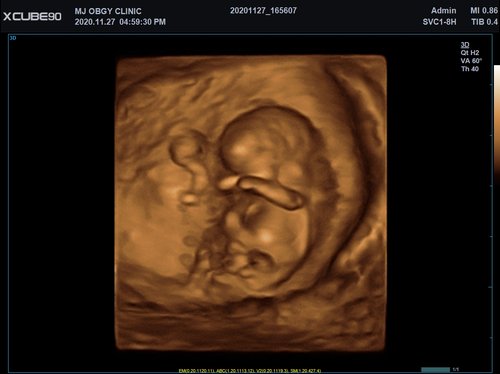

Mit dem X-CUBE 90 beginnt ALPINION eine neue Generation an Farbdopplersystemen, die X- CUBE Serie. Mit Bildverarbeitungstechnologien eines Premiumsystems und neuen Breitband- Schallköpfen mit X + Crystal Signature™ Technologie wartet das neue X-CUBE 90 auf.

Neben der hohen Bildqualität liegt ein weiterer Fokus auf der Vereinfachung und der Anpassung der Bedienung des Ultraschallgeräts. Individuell programmierbare Workflows und ein erweitertes Spektrum an automatisierten Messungen ermöglichen ein schnelleres und genaueres Arbeiten in jeder Situation.

X + Architecture

Die X + Architecture ist eine erstklassige Imaging-Plattform, die durch die Kombination von X + Crystal Signature™, der Schallkopftechnologie mit hoher Sensitivität und Breitbandigkeit, und X + FIT, ALPINIONs modernste Beamforming- und Datenverarbeitungstechnologiengeschaffen wurde. X + FIT ist eine neue Technologie, die den Schallstrahl scharf fokussiert sendet, ein großes Datenvolumen empfängt und mit hoher Geschwindigkeit verarbeitet. Darüber hinaus nutzt X + Crystal Signature™ Einkristalle und unser eigenes entwickeltes Schallkopfmaterial, um eine hervorragende Brillanz zu erzielen und die Diagnosemöglichkeiten zu erweitern.

eXpanded Capability

Das X-CUBE 90 bietet modernste Technologien für eine objektive und akkurate Diagnose. Intelligente klinische Module heben das System auf ein neues diagnostisches Niveau. Es erweitert Ihre Fähigkeiten und die Bandbreite Ihrer Möglichkeiten. Dazu gehören Module wie MicroView, point Shear Wave Elastographie (pSWE), oder auch die Kontrastmittelsonographie.